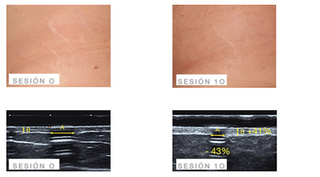

Before and after m.pen[pro]

DOUBLE CHIN

m.pen [pro] + x.prof organic silicon 1%, x.prof l-carnitine and x.prof melilot and rutin extract

Sex: female

Age: 47 years

SPEED according to tolerance DEPTH < 1 mm